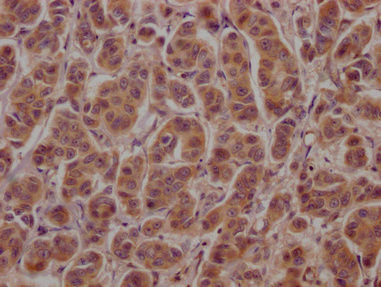

• IHC image of CSB-PA002272LA01HU diluted at 1:100 and staining in paraffin-embedded human breast cancer performed on a Leica BondTM system. After dewaxing and hydration, antigen retrieval was mediated by high pressure in a citrate buffer (pH 6.0). Section was blocked with 10% normal goat serum 30min at RT. Then primary antibody (1% BSA) was incubated at 4°C overnight. The primary is detected by a Goat anti-rabbit polymer IgG labeled by HRP and visualized using 0.05% DAB.